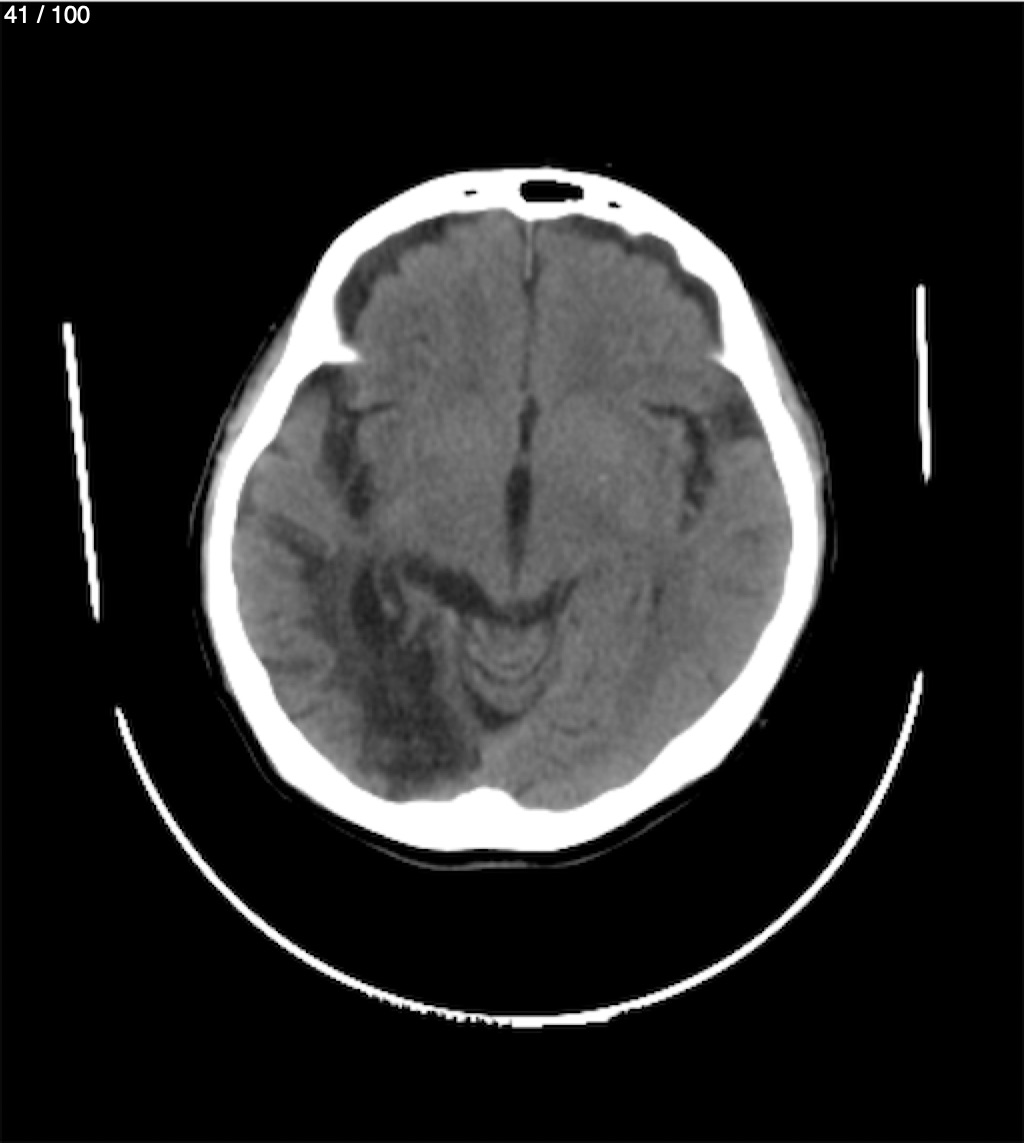

Catarino Perez Escobar 85A - T.C Craneo